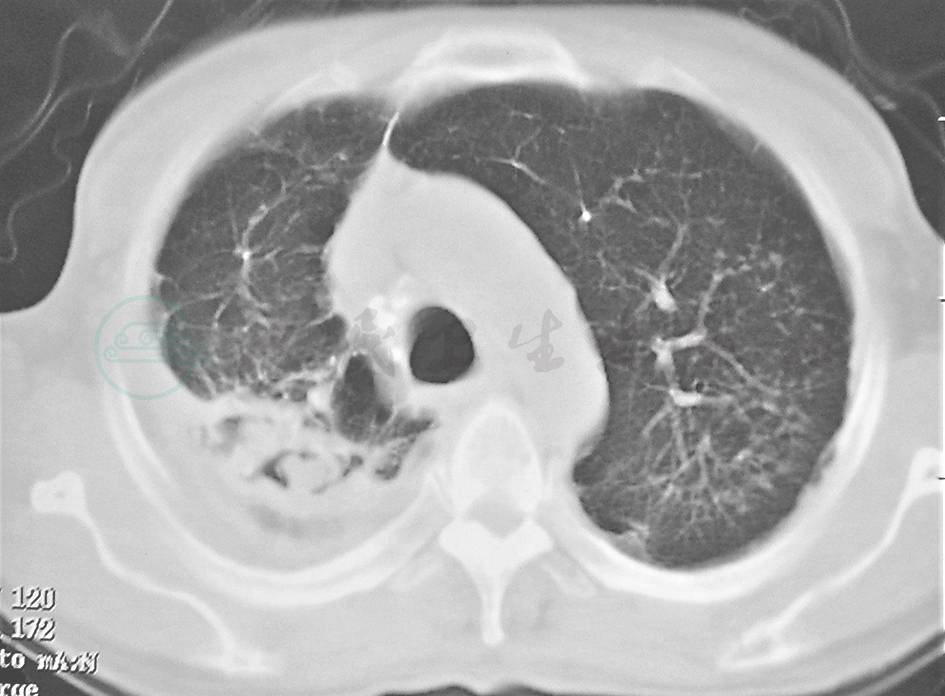

特殊感染:本例患者外观消瘦,双肺多发病变,抗感染治疗后病情反复,须注意排除肺结核,尤其肺结核所致干酪性肺炎(图3、图4)。肺结核的胸部影像学表现可为实变,密度多不均匀(中心密度高,边缘模糊),其中可有多个融合区,好发于上叶尖后段和下叶背段,病变肺段体积缩小,胸廓塌陷,大多数同时可见空洞、钙化、卫星灶等,由于沿支气管传播,病变多在相邻的多叶段内。本例患者的胸部影像学表现与此不符,可进一步查PPD、T-SPOT检测、痰抗酸染色等以排除该病。

图3 干酪性肺炎胸部影像学表现

胸部CT可见右上肺大片高密度实变影,伴支气管充气征

图4 干酪性肺炎胸部影像学表现

胸部CT可见双中下肺可见较弥漫斑片状高密度影,病灶沿支气管分布,并见树芽征